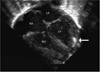

A premature infant with fetal myocardial and abdominal calcifications and factor V Leiden homozygosity

We present a premature male neonate with confirmed factor V Leiden deficiency diagnosed prenatally with cardiac and abdominal calcifications. Our patient's findings suggest that clinicians consider thromboembolic conditions when multiple fetal calcifications are visualized.